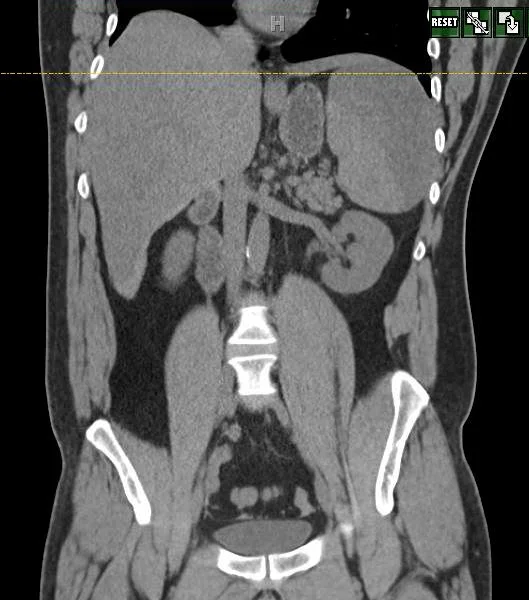

A 37 y.o. male fell off his segway one week pta. a ct of the abdomen is shown below.

Hint: It is normal

Our patient had a delayed rupture of the spleen.  This is defined as an injury followed by a negative CT and then a proven rupture of the spleen at a later date. Our patient  was riding on a Segway when the R wheel caught on a wall.  He had to step off in front of it.  The Segway hit his leg and and he swung around so it hit his upper abdomen causing him to fall to the ground.  He had the CT shown which was read as normal.  Three days later he began to complain of “muscle spasms” .  Ten days after the injury he came in with L flank pain and had the second CT showing a large subcapsular hematoma of the spleen.